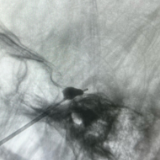

考虑到谭奶奶年事已高、合并多种基础疾病,脑病科医疗团队联合麻醉科团队开展多学科联合会诊,综合评估其身体状况与病情后,决定采用C臂辅助下经皮穿刺三叉神经球囊压迫术这一微创方案。

该手术无需开颅,仅用一根细穿刺针,从口角旁穿刺至颅底,将微小球囊置入特定部位,阻断痛觉神经传导即可,全程仅耗时30分钟。手术创伤极小,只留下一个针眼,无需缝合。术后,谭奶奶的疼痛立刻缓解,困扰她两年多的病痛终于消失。